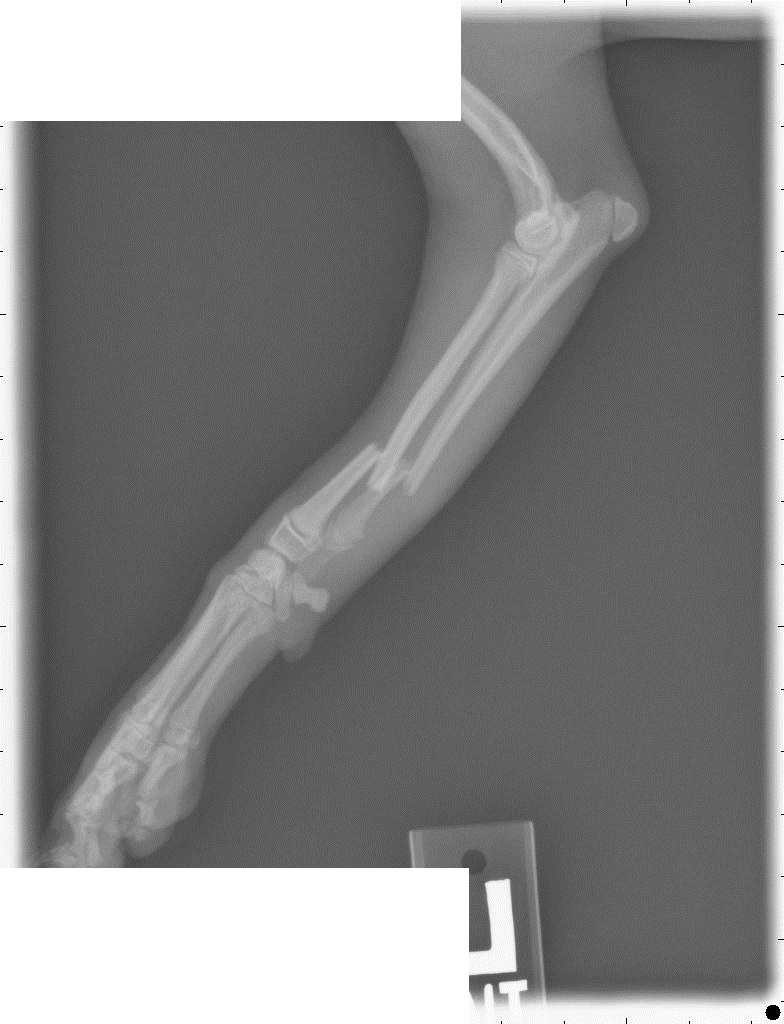

Ну да, у нас тоже счастливо скакала. И вот на чем: (первый снимок сделан перед операцией, после снятия гипса)

Сходили снова к вету, сняли повязку. Лапа выглядит нормально, собака на нее понемногу наступает. Про зону роста вет сказал, что она начинается на несколько миллиметров после последнего болта. Пластину все-таки будут снимать через какое-то время. В общем-то, принципиально это тот же аппарат Илизарова с поперечными винтами, только внутри. Локтевую кость не скрепили, сказали, что без надобности.